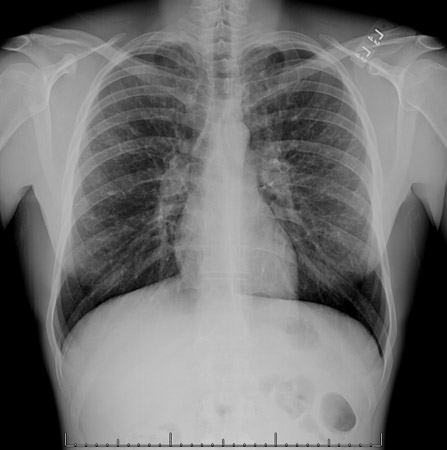

Chest x-ray

A chest x-ray should be obtained early in the evaluation of chronic cough.[38] Although it is not diagnostic of the most common causes, findings may quickly divert the evaluation to causes of greater gravity, such as structural lung diseases. These include lung cancer, pulmonary fibrosis, tuberculosis, bronchiectasis, pneumonia, aspiration, and sarcoidosis.[Figure caption and citation for the preceding image starts]: Chest x-ray showing hyperinflation in a patient with COPD. The hyperinflation is caused by the emphysema component of COPD, rather than the chronic bronchitis that underlies symptoms of coughFrom the personal collection of Dr M. A. Sharifabadand, SUNY at Stony Brook School of Medicine, Department of Pulmonary and Critical Care Medicine, Mineola, New York and Dr J. P. Parsons, The Ohio State University Medical Center, Columbus; used with permission [Citation ends].com.bmj.content.model.assessment.Caption@65a65855[Figure caption and citation for the preceding image starts]: Chest x-ray showing multiple miliary lung metastases (arrows). The primary tumour was a thyroid carcinomaE. Dick, Student BMJ. 2001;9:10-12 [Citation ends].com.bmj.content.model.assessment.Caption@25657fee[Figure caption and citation for the preceding image starts]: Chest x-ray showing left hilar carcinoma (arrow)From: E. Dick, Student BMJ. 2000;8:358-360 [Citation ends].com.bmj.content.model.assessment.Caption@567b9fef[Figure caption and citation for the preceding image starts]: Chest x-ray showing a cavitating right hilar carcinoma (arrow)E. Dick, Student BMJ. 2001;9:10-12 [Citation ends].com.bmj.content.model.assessment.Caption@3d6fa55[Figure caption and citation for the preceding image starts]: Chest x-ray in a patient with bronchogenic carcinoma showing a left-sided pleural effusionFrom: R. Thakkar, Student BMJ. 2001;9:458 [Citation ends].com.bmj.content.model.assessment.Caption@5b46acec[Figure caption and citation for the preceding image starts]: Chest x-ray showing interstitial fibrosis in a patient with amiodarone pulmonary toxicityFrom the personal collection of Dr A. Pataka and Professor P. Argyropoulou, Aristotle University, Thessaloniki, Greece; used with permission [Citation ends].com.bmj.content.model.assessment.Caption@2c3c94b0[Figure caption and citation for the preceding image starts]: Chest x-ray showing pulmonary tuberculosis with cavitationFrom the personal collection of Dr M. Narita, Department of Pulmonary and Critical Care Medicine, University of Washington [Citation ends].com.bmj.content.model.assessment.Caption@3dd7f84b[Figure caption and citation for the preceding image starts]: Chest x-ray showing multiple discrete nodules throughout both lungs (one of which is circled) in a patient with miliary tuberculosisE. Dick, Student BMJ. 2001;9:10-12 [Citation ends].com.bmj.content.model.assessment.Caption@23fa6365[Figure caption and citation for the preceding image starts]: Chest x-ray with lack of normal tapering producing a tram line in a patient with bronchiectasisFrom the personal collection of Dr S.M. Bhorade, University of Chicago Medical Center; used with permission [Citation ends].com.bmj.content.model.assessment.Caption@36b415f2[Figure caption and citation for the preceding image starts]: Chest x-ray with dilated and thickened airways in a patient with bronchiectasisFrom the personal collection of Dr S.M. Bhorade, University of Chicago Medical Center; used with permission [Citation ends].com.bmj.content.model.assessment.Caption@78e208fa[Figure caption and citation for the preceding image starts]: Chest x-ray showing increased opacification of the right perihilar region and superior segment of the right lower and upper lobes consistent with worsening aspiration pneumoniaFrom the personal collection of Dr R. Kanner, University of Utah School of Medicine [Citation ends].com.bmj.content.model.assessment.Caption@71be2c1f[Figure caption and citation for the preceding image starts]: Portable chest x-ray with bibasilar opacities, worse on the right than the left, in a patient with hospital-acquired pneumoniaFrom the personal collection of Dr F. W. Arnold, Division of Infectious Diseases, Department of Medicine, University of Louisville School of Medicine [Citation ends].com.bmj.content.model.assessment.Caption@2c704497[Figure caption and citation for the preceding image starts]: Chest x-ray showing early ill-defined opacities of the right upper lobe above the minor fissure consistent with early changes of aspiration pneumoniaFrom the personal collection of Dr R. Kanner, University of Utah School of Medicine [Citation ends].com.bmj.content.model.assessment.Caption@23fa54d0[Figure caption and citation for the preceding image starts]: A. Portable upright chest x-ray before aspiration; B. Chest x-ray 1 hour after aspiration, showing bilateral diffuse alveolar infiltrates, worse at the bases on the right sideFrom the personal collection of Dr S. Murgu and Dr H. Colt, University of California at Irvine Medical Center [Citation ends].com.bmj.content.model.assessment.Caption@7860be3a[Figure caption and citation for the preceding image starts]: Chest x-ray showing bilateral hilar adenopathy in a patient with sarcoidosisFrom the personal collection of Dr M.P. Muthiah, Division of Pulmonary and Critical Care and Sleep Medicine, University of Tennessee [Citation ends].com.bmj.content.model.assessment.Caption@31e94b4e